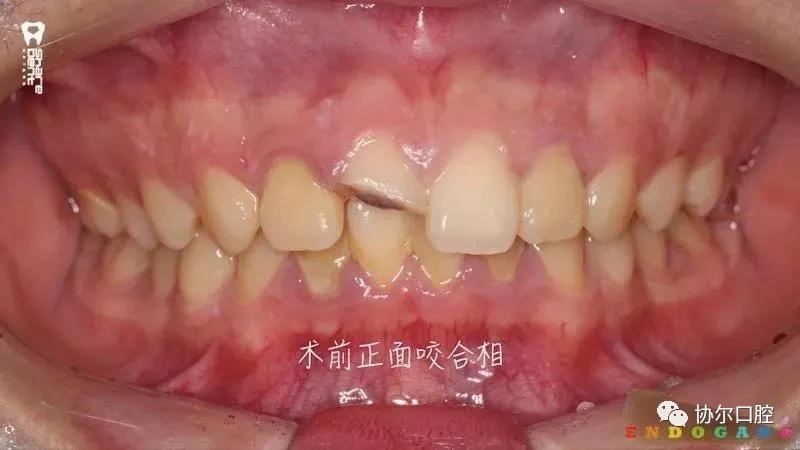

好多朋友都在问有没有前牙外伤折断后美塑树脂断牙显微再接的病例,正当小编“愁眉苦展”时,喻刚老师雪中送炭来了。15岁青少年断牙24小时,破镜重圆,修旧如旧。

病例刷一波